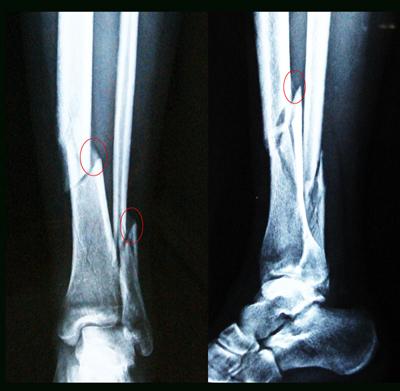

骨裂后两个骨头之间的位移,没有产生特别大的变化,所以有的时候从X光或者CT上能看到一个缝,这个一般来说我们就称之为骨裂。